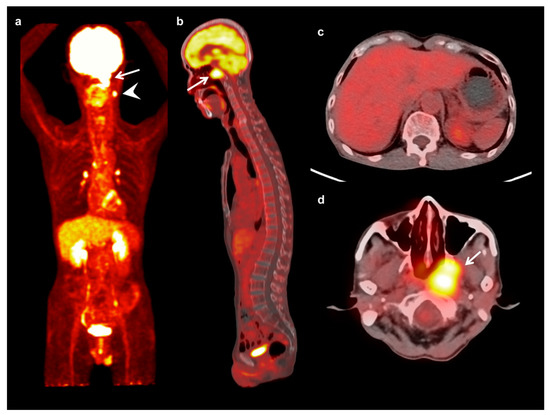

Figure 1.

Maximum intensity projection (a) and sagittal (b) FDG PET images and fused transaxial FDG PET/CT images (c,d) of a 64-year-old man with nasopharyngeal cancer. A 3 cm-sized mass in the left nasopharynx showed intensely increased FDG uptake (arrow) (maximum SUV 9.53, metabolic tumor volume 28.83 cm3, and total lesion glycolysis 132.62 g) with ipsilateral neck lymph node metastases (arrowhead). Serum CRP level, NLR, and PLR of the patients were 3.02 mg/dL, 2.53, and 212.38, respectively. On FDG PET/CT, only a mild degree of FDG uptake was shown in the bone marrow (BM SUV of 1.13 and BLR of 0.64). The patient was clinically diagnosed with T3N1, stage III, and underwent concurrent chemoradiotherapy. The patient has not experienced cancer progression during 48.8 months of follow-up.